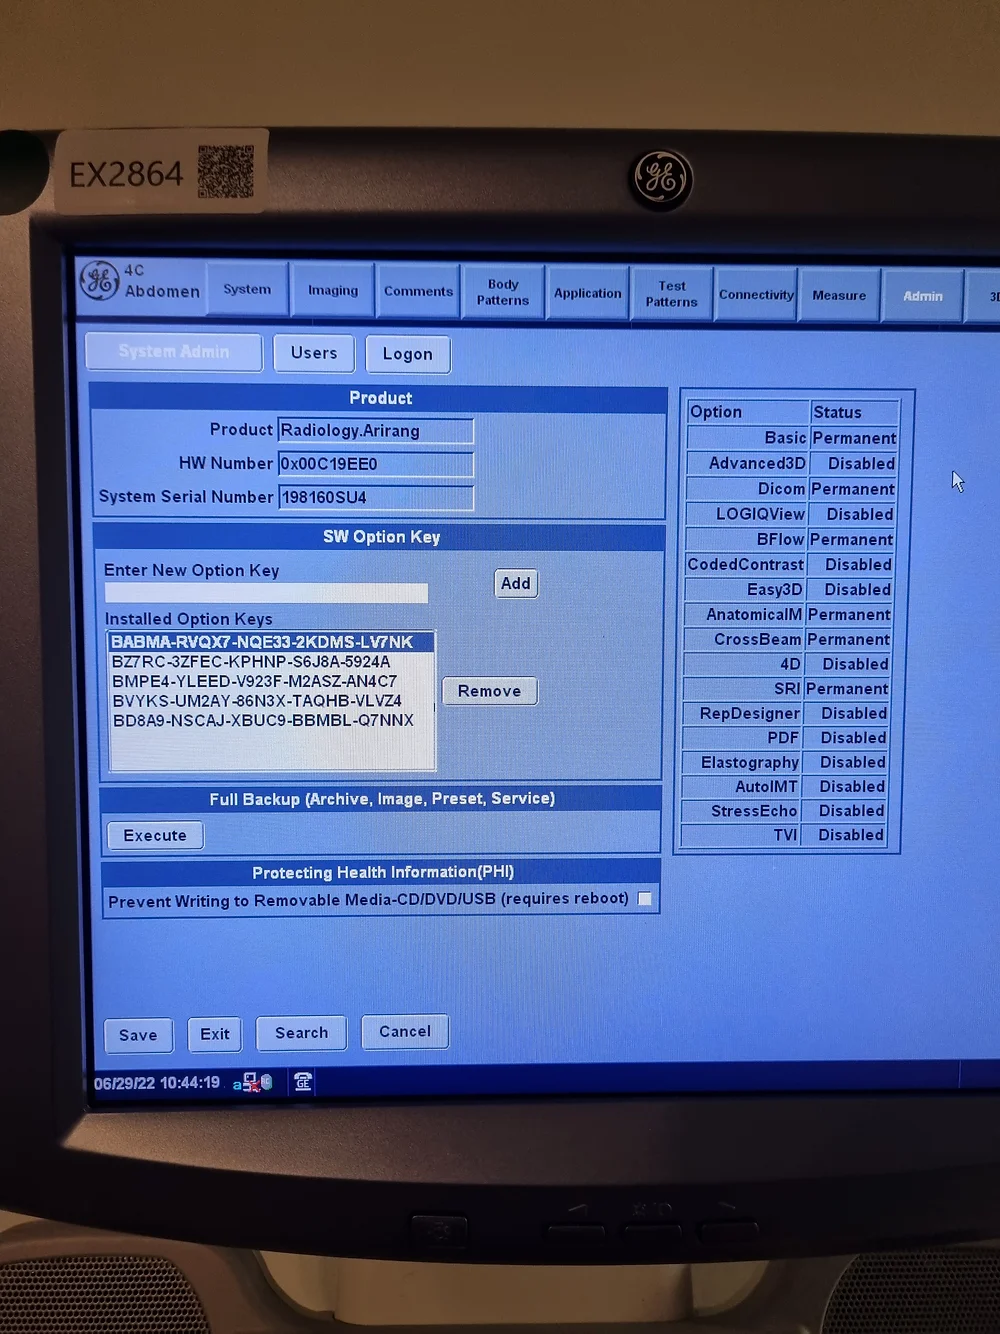

- Advanced Imaging Capabilities: Experience the power of 3D/4D imaging with the LOGIQ P5, enabling clinicians to obtain detailed and comprehensive insights into anatomical structures and pathology.

- Exceptional Performance: Despite its compact size, the LOGIQ P5 stands out as one of the most robust systems in its price range, offering features like CrossXBeam composite imaging, cardiac imaging, and speckle reduction for superior diagnostic accuracy.

- Comprehensive Imaging Solutions: From automatic tissue optimization to coded harmonic imaging and high pulse repetition rate, the LOGIQ P5 is equipped with a range of innovative technologies to enhance imaging performance across diverse clinical applications.